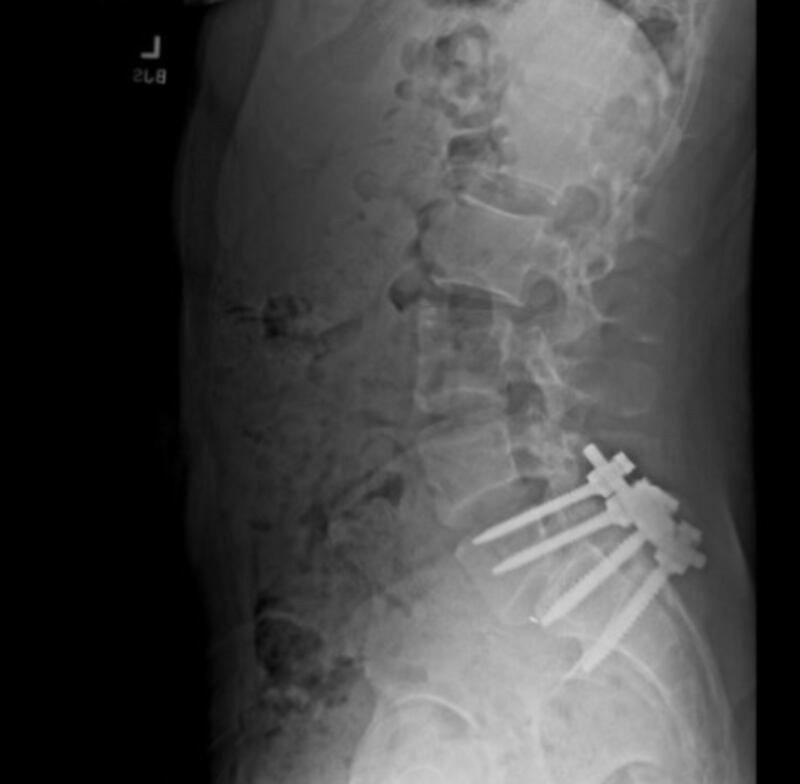

After the op, Mangione sent Martin an x-ray photo of his spine. He also posted an x-ray of metal pins fitting into a spine on his X account.

Martin said the spine’s appearance worried him and he texted Mangione to ask how he was doing.